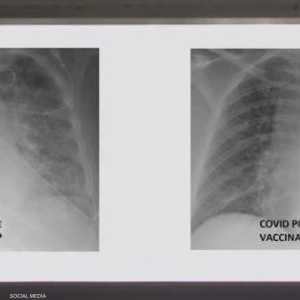

وقالت صحيفة "نيويورك تايمز" الأميركية إنه على الرغم من أن اللقاحات المتوفرة حاليا ما تزال فعالة بشكل ملحوظ ضد "كوفيد-19" ومتحوراته، إلا أن التوصيات الجديدة الخاصة بالملقحين أوقعت الكثير من الناس في حيص بيص.

وبينما تظهر الأبحاث الجديدة أن الأشخاص الذين تم تطعيمهم يمكن أن يصابوا وينقلوا العدوى، من المهم أن نتذكر أن هذه الحالات تظل نادرة، وأن غير الملقحين هم الذين يصابون وينشرون الفيروس على نطاق أوسع.